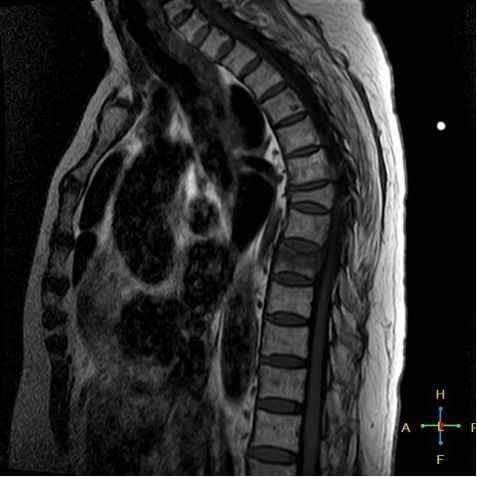

3 恶性压缩性骨折 椎体上下径变窄而前后径增大,椎体后部皮质后突,后角一般表现圆钝,无上翘,常呈球形突出,致椎管狭窄,即膨胀性盘状破坏,硬膜囊和脊髓受压。

——恶性压缩性骨折MR信号特点—— 由于肿瘤组织的侵犯,T1WI上椎体呈弥漫性低信号,T2WI呈高信号,增强扫描呈明显不均匀强化。

转移瘤 椎弓根改变:椎弓根膨大仅见于恶性压缩性骨折,故为其特异性,可作为鉴别诊断的依据。

椎旁软组织肿块:在转移瘤中,受累椎体周围多出现分叶状或肿瘤样软组织肿块,此征象仅见于恶性压缩性骨折。故,椎旁薄环状软组织与瘤样软组织肿块是鉴别骨折性质较有特征性的征象。